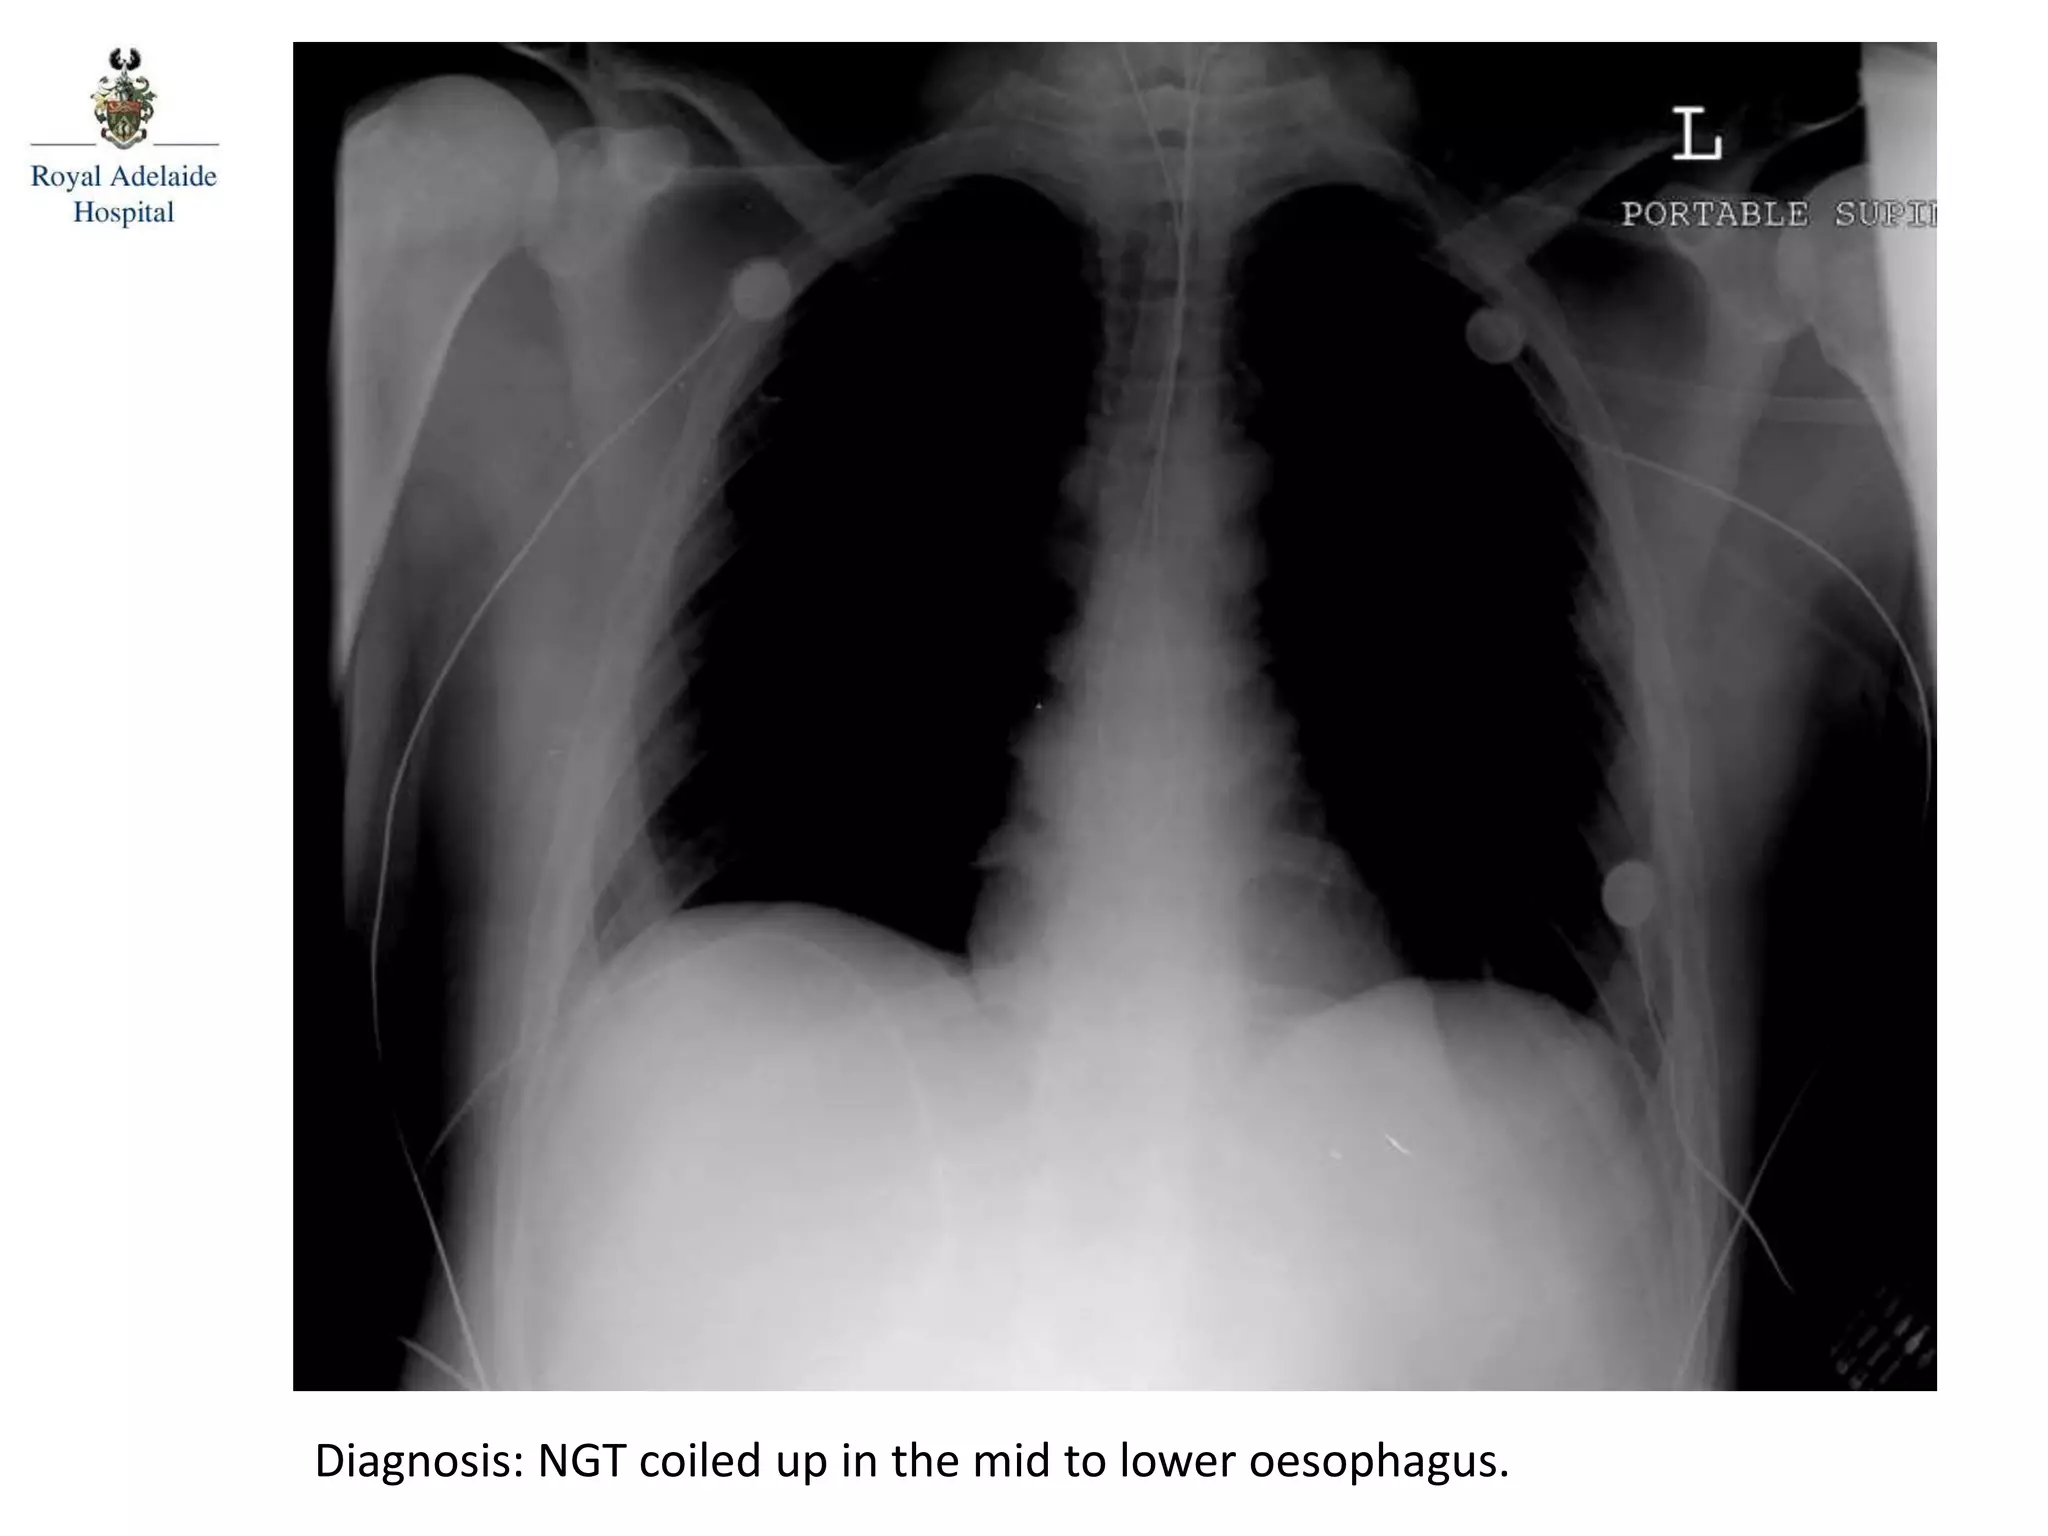

Diagnosis: NGT coiled up in the mid to lower oesophagus.